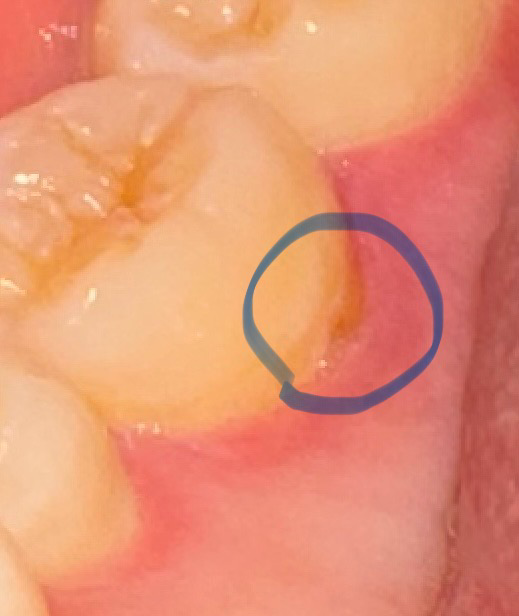

사진 속 치아 치석인가요? 혹은 충치인가요?

입을 벌려 확인해봤을때 약간 갈색비슷한 색이 보여서 썩은 줄 알고 확인해봤더니 치석같기도 하네요

• 2번 째 사진

사진에 보이는건 치석은 아니고 치경부 마모증때문에 잇몸이 내려가면서 치아의 뿌리가 노출된거 같습니다.

해당부분에 생긴 것으로 봤을 때 치석일 가능성이 높습니다만 치과에서 정확한 검진을 받아보시는 게 좋습니다.

충치의 가능성은 낮고 치태와 치석으로 보입니다 스케일링을 받은지 오래되었다면 스케일링을 한번 받아보시면 좋을 것 같습니다